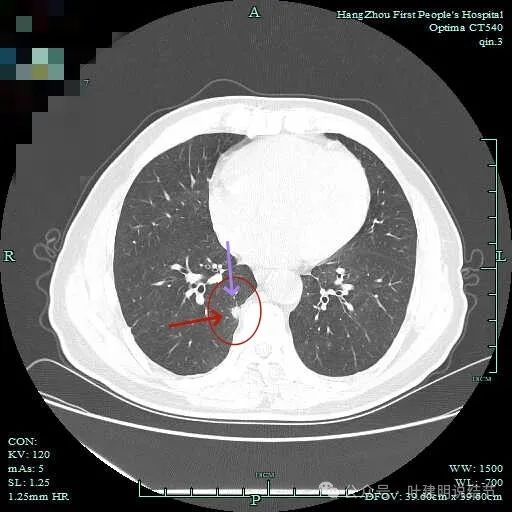

有细小血管进入,但说不上异常增粗。病灶仍是小片状,条状。

磨玻璃成分密度淡且界欠清,整体就是条索状弯曲的。

上图见细毛刺明显。

病灶实性伴细毛刺,与脊柱间有间隙在。

病仍明显,从上到下,觉得应该是成片的。

表面不平毛刺,实性密度为主。

微小血管有,但无异常增粗。

病灶实性,边缘不光滑。

实性密度,片状,条状。

病灶实性,缺乏膨胀性。

上图呈结节状,表面不平,有少许磨玻璃成分。

结节状,密度高,边缘欠光滑。

与脊柱之间有间隙,表面有细毛刺。

表面不平,似有细支气管截断征。

边缘不平毛糙。

像慢性炎似的。

瘤肺边界欠清。

边缘区淡磨玻璃密度。